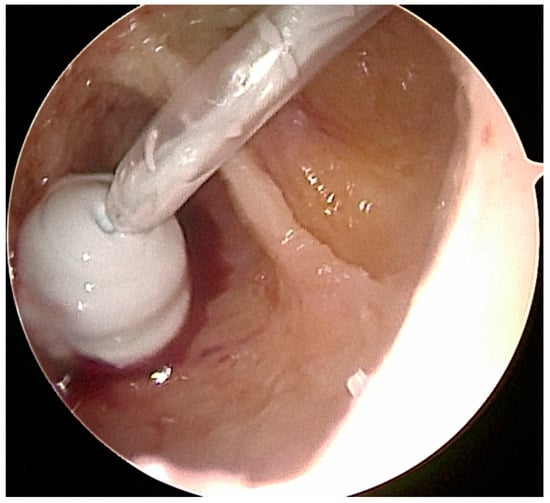

Figure 4.

A Hartmann ear septum borrowed from ENT surgery facilitated the insertion of the allogeneic cancellous bone into the bone cavity.